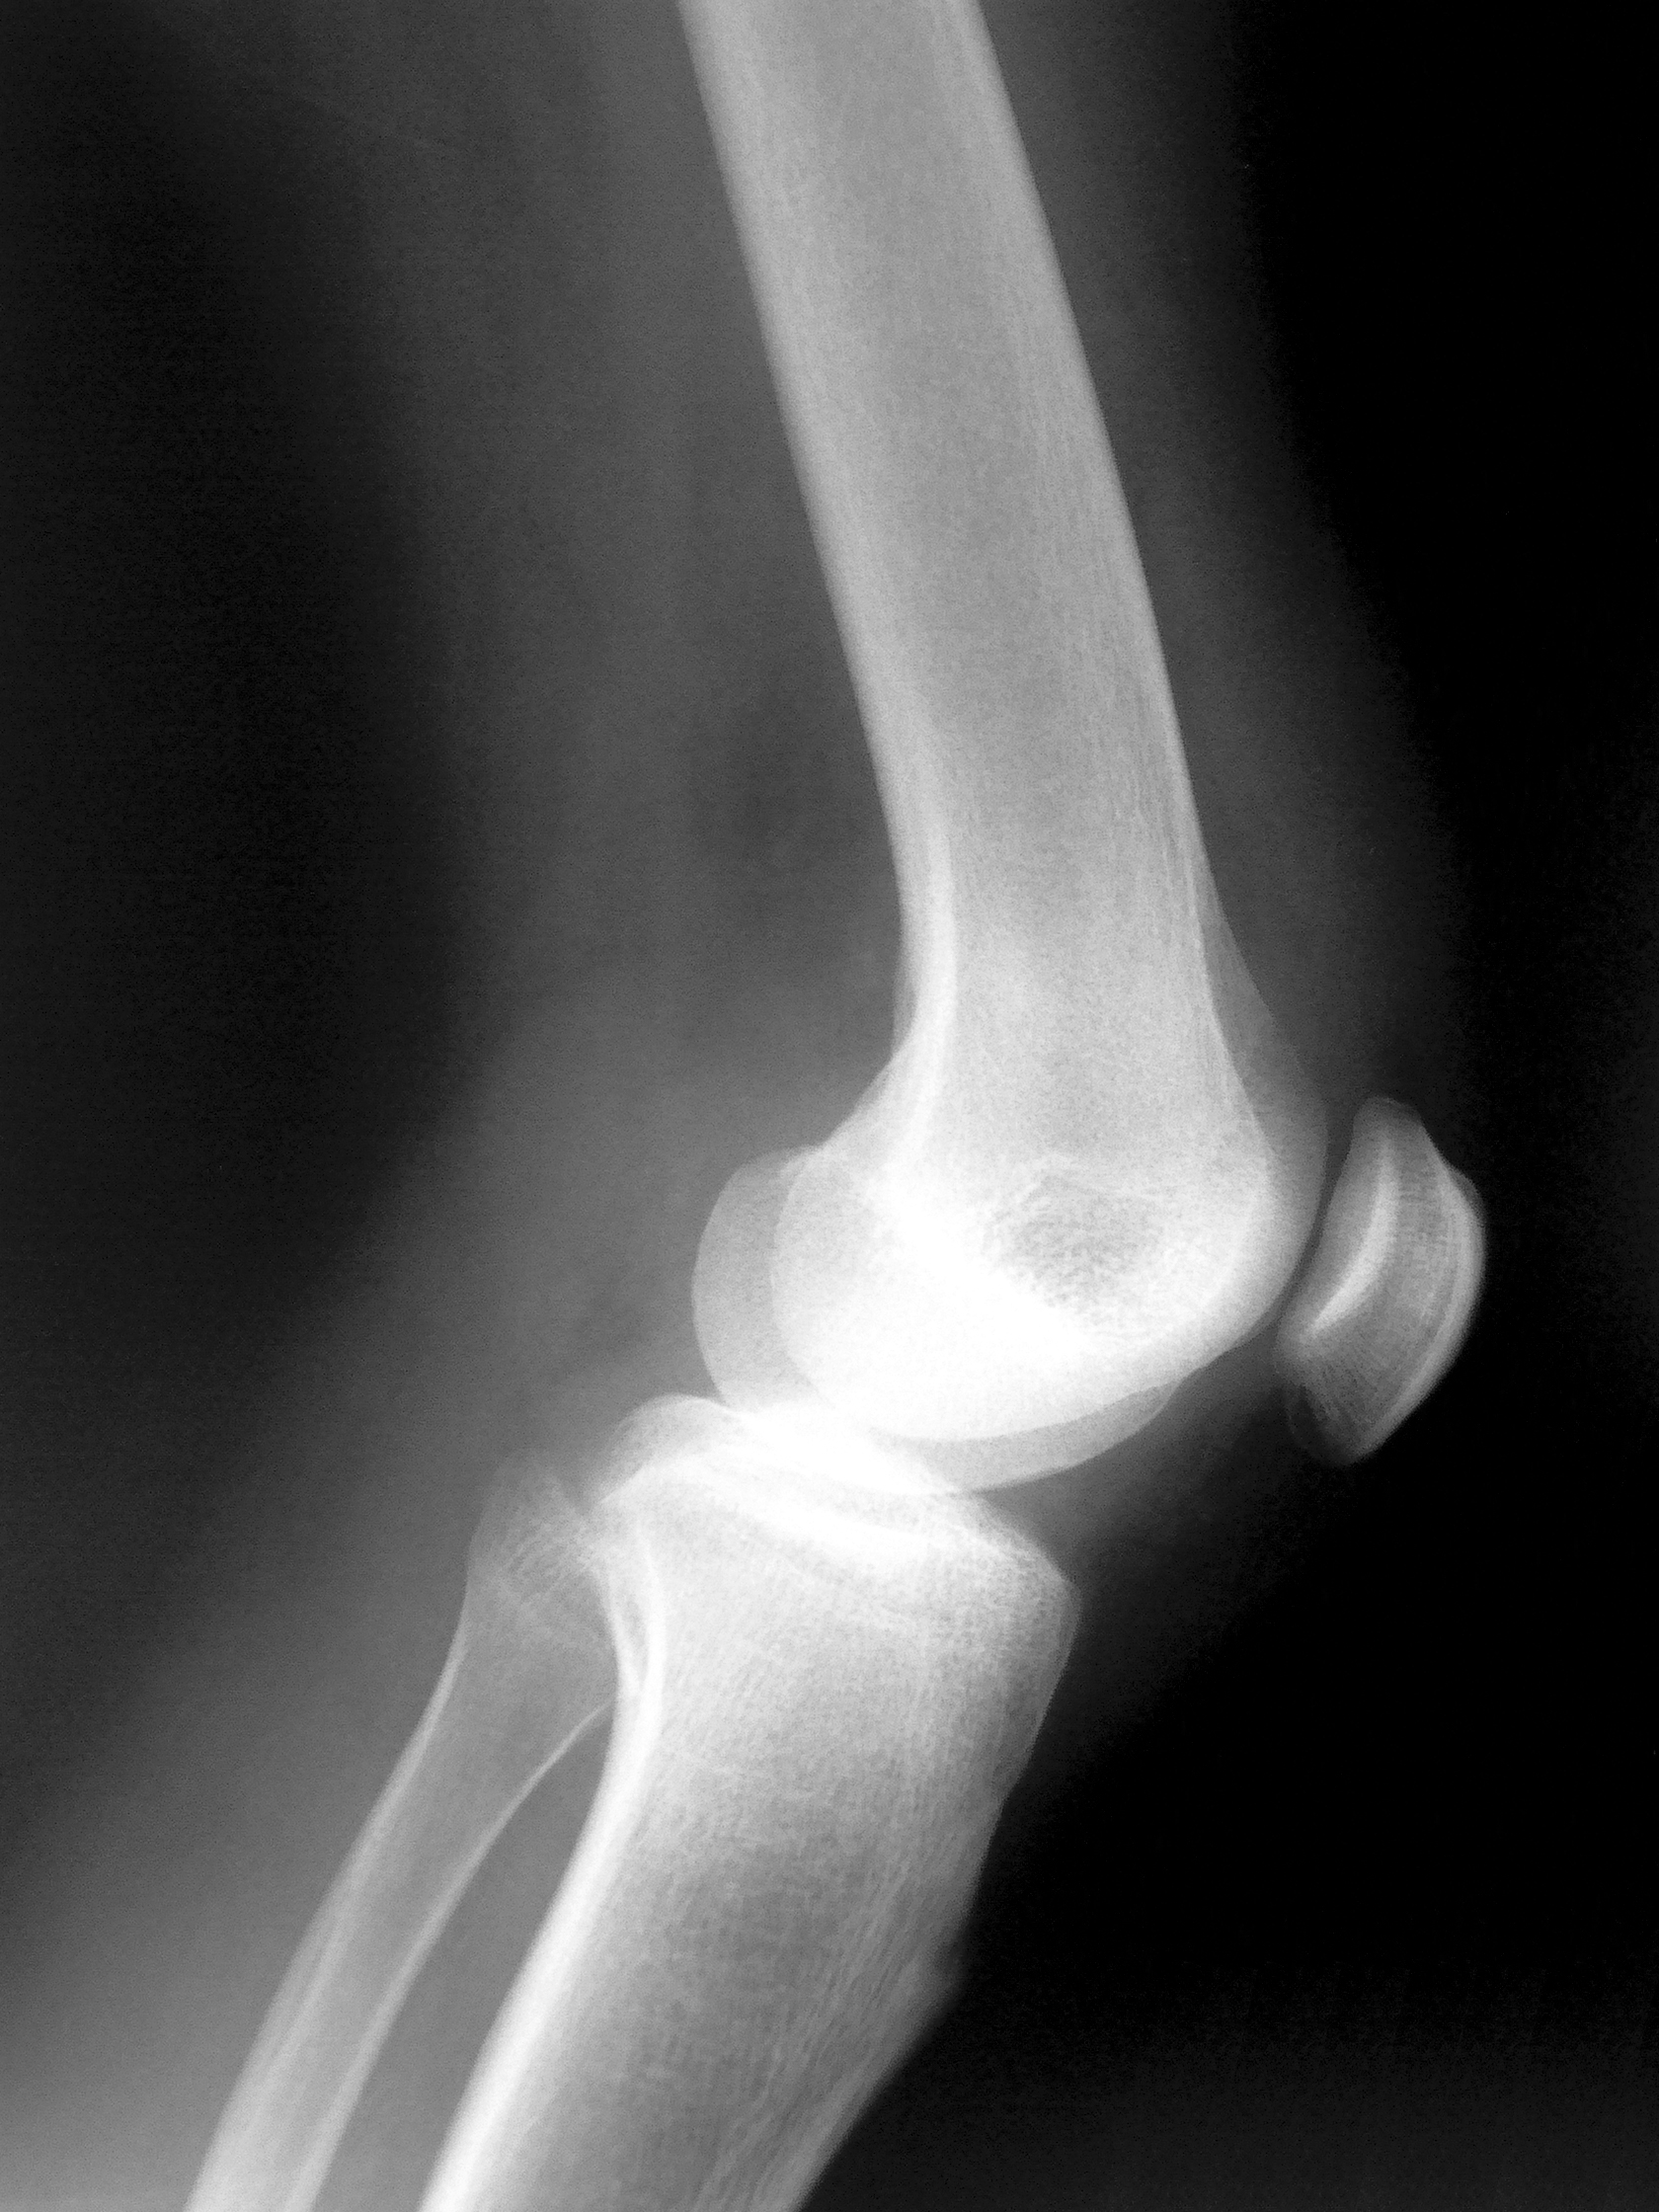

- Pain in other joints, such as the knees, hips and shoulders